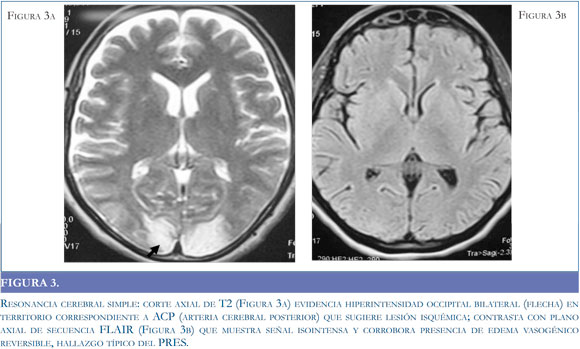

La tomografía puede no ser el método de elección en consideración a sus características operativas, pero es un recurso de fácil acceso para la aproximación diagnóstica. Si bien la tomografía puede ser negativa en la etapas tempranas del síndrome (39), está documenta la presencia de lesiones hipodensas habitualmente simétricas1 en la sustancia blanca de los territorios posteriores y gangliobasales (34) (Figuras 1 a y b); con el desenlace clínico de la patología, las imágenes tomográficas muestran una resolución de las hipodensidades descritas en el momento de mayor intensidad clínica (Figuras 2 a y b).